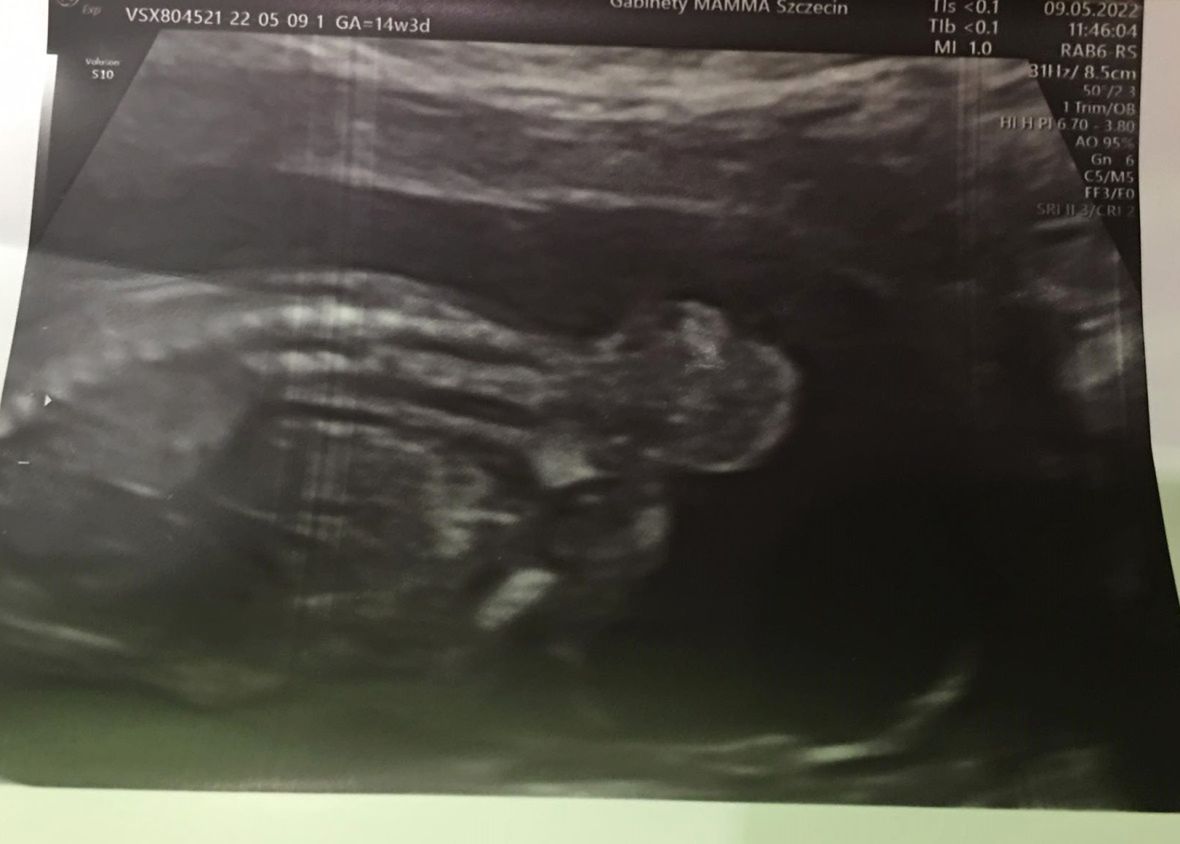

- W 13. tygodniu ciąży udałam się na kontrolne badanie USG. Chciałam dowiedzieć się, jaka jest płeć dziecka, czy maluch dobrze się rozwija. Badanie trwało bardzo długo, wiedziałam, że coś jest nie tak. Lekarka powiedziała mi, że moja córeczka ma guza na kości ogonowej. Wtedy zmiana miała cztery centymetry. W opisie badania przeczytałam, że "istnieje ryzyko dalszego nasilania niewydolności krążenia, do wewnątrzmacicznego obumarcia płodu włącznie". Byłam przerażona. Zaproponowano mi, abym w 15. tygodniu ciąży wykonała amniopunkcję (metoda diagnostyczna, która polega na nakłuciu igłą jamy owodni - przyp. red.) - wspomina 18-letnia Wiktoria w rozmowie z nami.

Badanie USG

Badanie USG © arch.prywatne